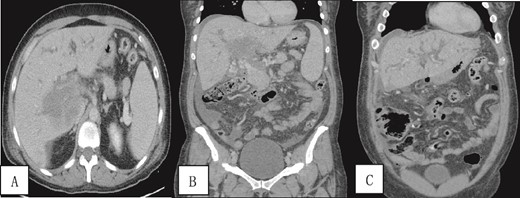

A contrast-enhanced CT scan of the abdomen and pelvis was done and revealed a dilated non-opacified main portal vein and superior mesenteric vein suggestive of thrombosis with periportal vascular congestion as well as a hypo-vascular geographic area with complex fluid density at the hilum of the liver and gallbladder fossa with dilated right and left hepatic biliary ducts. It also showed mild splenomegaly, colonic diverticulosis, and mild ascites mainly in the right iliac fossa. The splenic vein appeared normal, and there were no imaging features of bowel ischemia (Fig. 1).

Contrast-enhanced CT scan of the abdomen and pelvis in (A) axial and (B, C) coronal sections obtained at the porto-venous phase showing a hypo-vascular geographic area with complex fluid density at the hilum of the liver with intrahepatic biliary dilatation. Non-opacification of the main portal vein with early cavernous transformation was noted as well as mild splenomegaly and ascites.